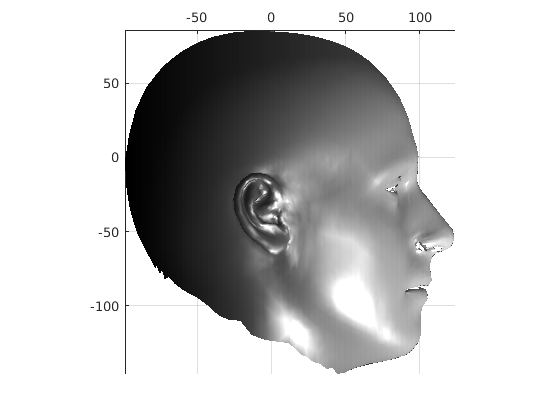

Toolsets to define normal appearance and therefore both assist with planning of surgery and define optimal outcomes from a range of surgical interventions are currently either crude or lacking. Therefore, the unit collected a large, high quality 3D image dataset of 1523 human heads. An example is given in Fig. 1 showing the 3D channel only on the left, and the 3D data with texture pasted on on the right. The data was collected over well-conserved demographics, and an age range of 1 to 89 years, see Fig. 2. The dataset was collected with the aim of developing a normal equivalent of the human cranium and face in order develop the tools to enhance patient experience following surgery. We plan to make the dataset publicly available in the near future.

Pose is normalised using the ECN method, and relies on the symmetry plane, ellipse centre and nasion position, as shown in Fig. 25. We then find a set of pseudo-landmarks on the cranial surface by 3D ray projection over a predefined set of angles, as shown in Fig. 26. The same processes are applied to a template mesh of the human head, so that it has the same set of both face and cranium landmarks.

The template mesh is then warped in a global affine sense, as shown in Fig. 27 to minimise the least-squares error between the two sets of landmarks, when the head scan is fixed in its canonical poose. After this initial stage, landmarks and pseudo-landmarks are used in the same way as any other mesh vertex, as they are potentially noisy, as seen in earlier results analysis. This contrasts with Amberg et al’s [11] approach where the influence of landmarks is gradually faded out.

Following this, OSNR ICP iterates over a set of decreasing mesh stiffnesses (typically 10), until the registration between the template and the scan is below some error or a maximum number of iterations is reached. Figure 28 shows a selection of template warp results. The template appears to be accurately warped onto the scan, at least in the normal direction of the surfaces, it is not possible to see error tangential to the surface. Furthermore, we have noted errors on some scans on the ears. To improve these we need a method of automatically landmarking the ears, which is an area for further work.

The first two modes of head variation are shown in figures 29 and 30. These include the cranial height / facial angle mode and the (almost) pure size mode, as seen in the sagittal profile model.